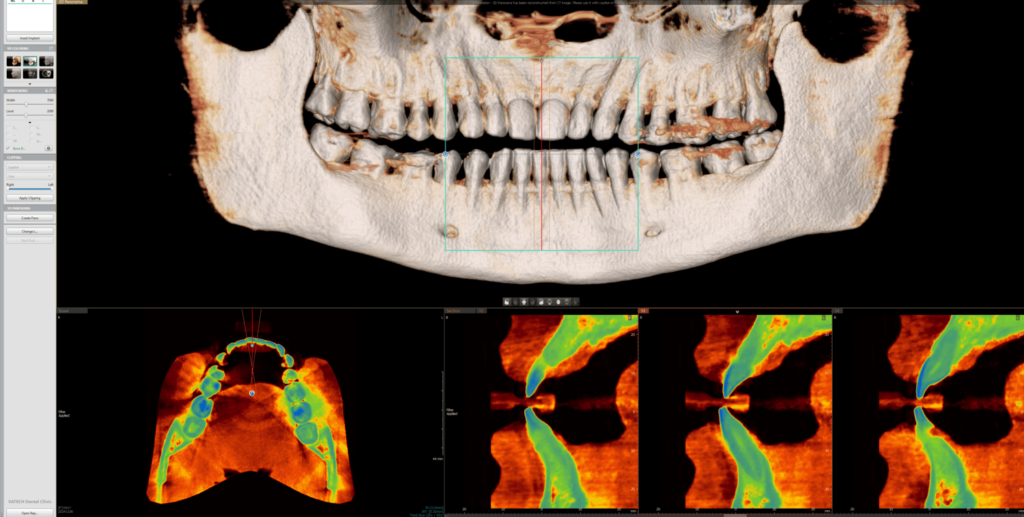

3D/CBCT (kompjuterizovana tomografija sa konusnim snopom) je napredni postupak snimanja u stomatološkoj radiologiji. Koristeći tehnologiju sličnu onoj kod standardnih medicinskih skenera, ali sa drastično smanjenom količinom zračenja, ova metoda pruža izuzetno precizne slike dentalnih struktura. 3D/CBCT omogućava pravljenje detaljnih trodimenzionalnih snimaka koji daju stomatologu potpuni uvid u zubne i koštane strukture, bez skrivenih ili iskrivljenih delova.

2D snimci su uobičajena vrsta snimanja koja prikazuje zube i vilice u jednoj ravni. To uključuje snimke pojedinačnih zuba, ortopane i slično. Za razliku od tradicionalnih 2D snimaka, 3D snimci zadržavaju pravilan odnos struktura, predstavljajući visinu, dužinu i širinu svih struktura u pravom odnosu 1:1.

Ova vrsta snimanja je posebno korisna za kompleksnije dentalne procedure, kao što su oralno-hirurške intervencije, postavljanje dentalnih implanata, ili tretman zuba sa višestrukim korenovima. Zahvaljujući 3D/CBCT snimcima, stomatolozi mogu precizno planirati i sprovoditi ove intervencije.